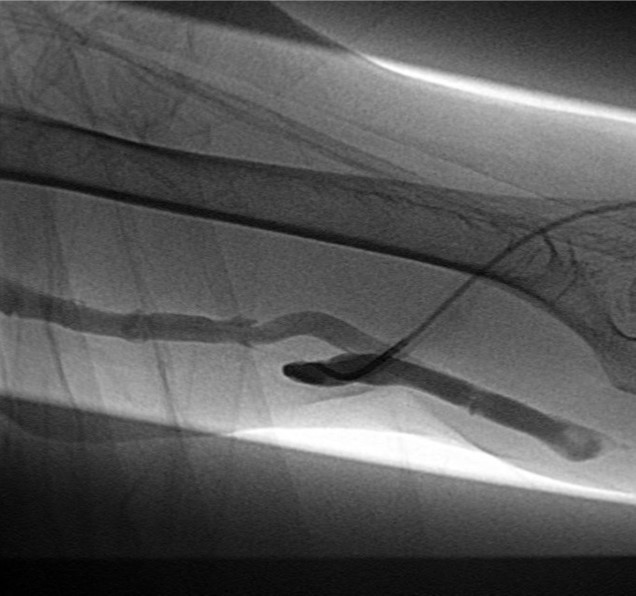

Fig. 4.

A-B. Failure of guide wire negotiation. Balloon tip was located in subcutaneous tissue.